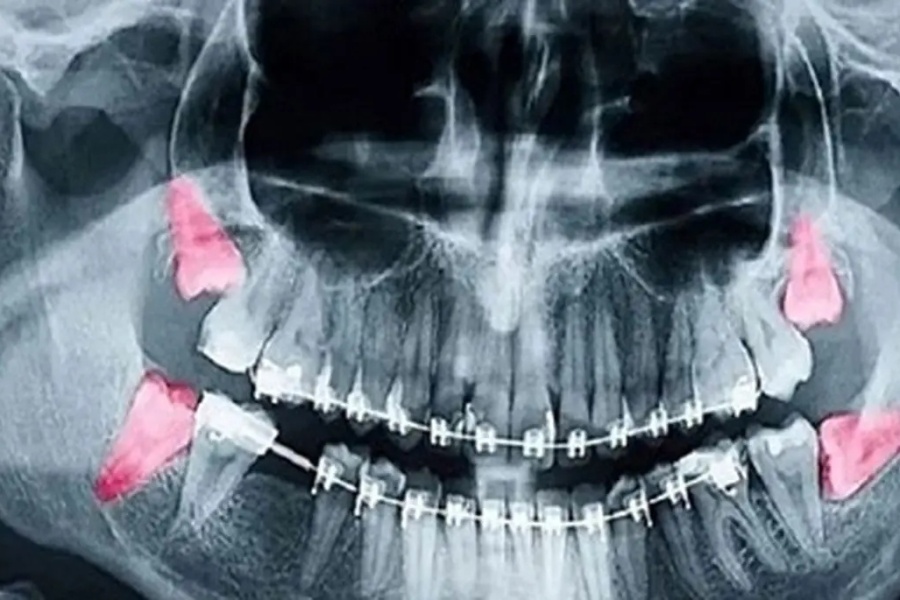

وی توضیح داد: میزان اشعه در رادیوگرافیهای دندانی بسیار پایین است؛ برای مثال، میزان اشعه در یک رادیوگرافی داخل دهانی معمولی حدود ۰.۰۰۵ میلیسیورت و تصویر پانورامیک (OPG) حدود ۰.۰۲ میلیسیورت است که به ترتیب هزار و ۲۵۰ برابر کمتر از حد مجاز ۵ میلیسیورت در دوران بارداری است.

وی تصریح کرد: در تصویربرداری پانورامیک دندان (OPG)، استفاده از محافظ تیروئید توصیه نمیشود.

وی توضیح داد که تابش پرتو از پشت سر بیمار انجام میشود و قرار دادن محافظ میتواند سایه در نواحی چانه، ریشه دندانهای قدامی یا فک پایین ایجاد کند؛ این موضوع کیفیت تصویر را کاهش داده و احتمال نیاز به تکرار عکس را افزایش میدهد که در نهایت میزان تابش اشعه را بالا میبرد.